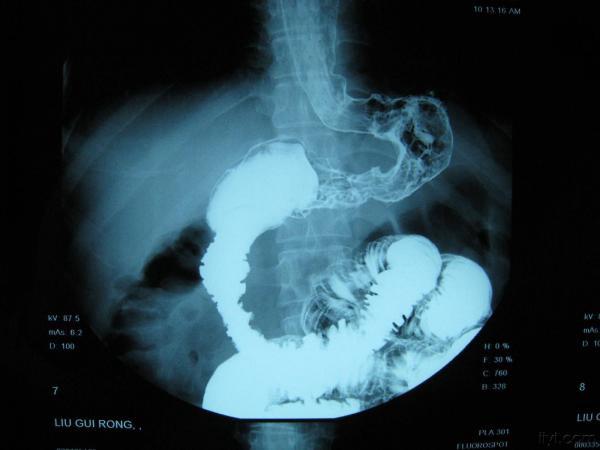

典型皮革胃!!!!

刚收一典型的皮革胃,准备明天腔镜下全胃切除,这个造影做的不错,希望对大家有帮助,只是照的不太好,见谅!!!

简单介绍一下皮革胃 皮革胃可以说是胃癌的一种,生长方式主要还是浸润式生长,最后使胃失去功能,使胃缩小,质地硬,像皮革一样,有称呼为革囊胃 临床上表现 1症状早期表现为上腹不适 2晚期可以摸到胃部 隆起 3贫血、消瘦、腹水等等!~ 检查: X线检查,造影 纤维胃镜, CT 细胞脱落病理检查 治疗: 手术行胃Ca 根治术 化疗 肠道营养 说的不太详细,以书本为主吧